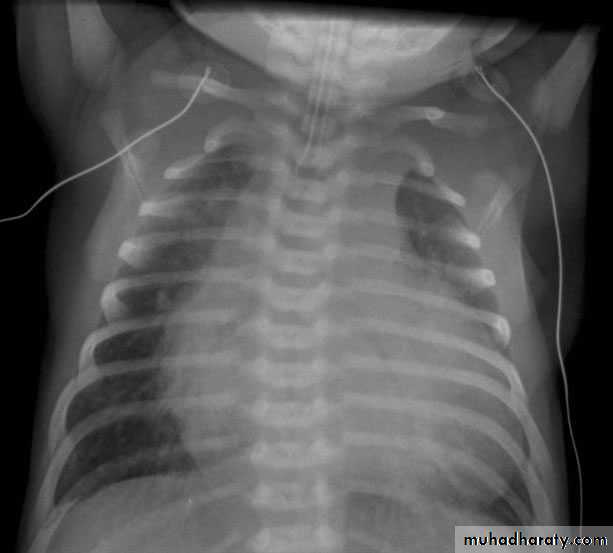

The absence of cardiomegaly on a chest x-ray usually rules out the diagnosis of heart failure.An Echocardiogram assesses the heart chamber sizes, measures myocardial function, and diagnoses congenital heart defects when present.

Diagnosis

- ECG-atrial enlargement, left ventricular or right ventricular enlargement; nonspecific T-wave changes-Chest x-ray--cardiomegaly, pulmonary congestion.

-Echocardiogram-dilatation of left atrium and left ventricle ± right ventricle and decreased contractility; decreased flow velocity across aortic valve with mitral regurgitation.